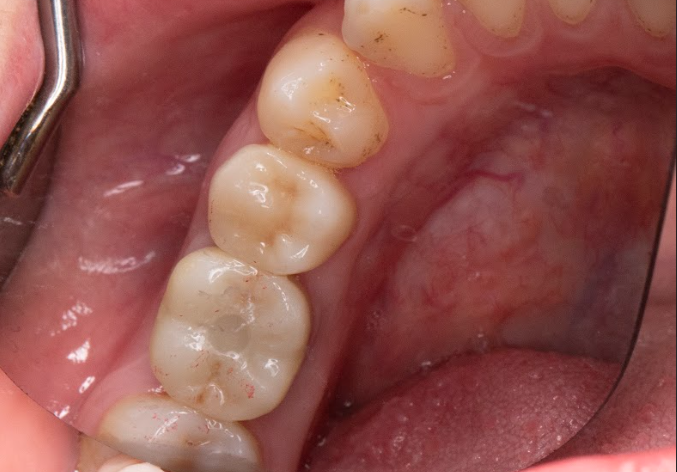

Bước 6: Gắn abutment & mão sứ

Sử dụng abutment cá nhân hóa CAD/CAM để tối ưu thẩm mỹ viền nướu.

Gắn mão sứ zirconia toàn khối, đảm bảo thẩm mỹ và độ bền cao.

Hoàn tất quy trình trồng răng Implant.

Kết quả sau khi trồng răng Implant

Khớp cắn ổn định, ăn nhai chắc chắn, thoải mái.

Không ảnh hưởng răng thật kế cận như cầu răng sứ trước đây.

Thẩm mỹ tự nhiên, nụ cười hài hòa, khó phân biệt đâu là răng Implant.